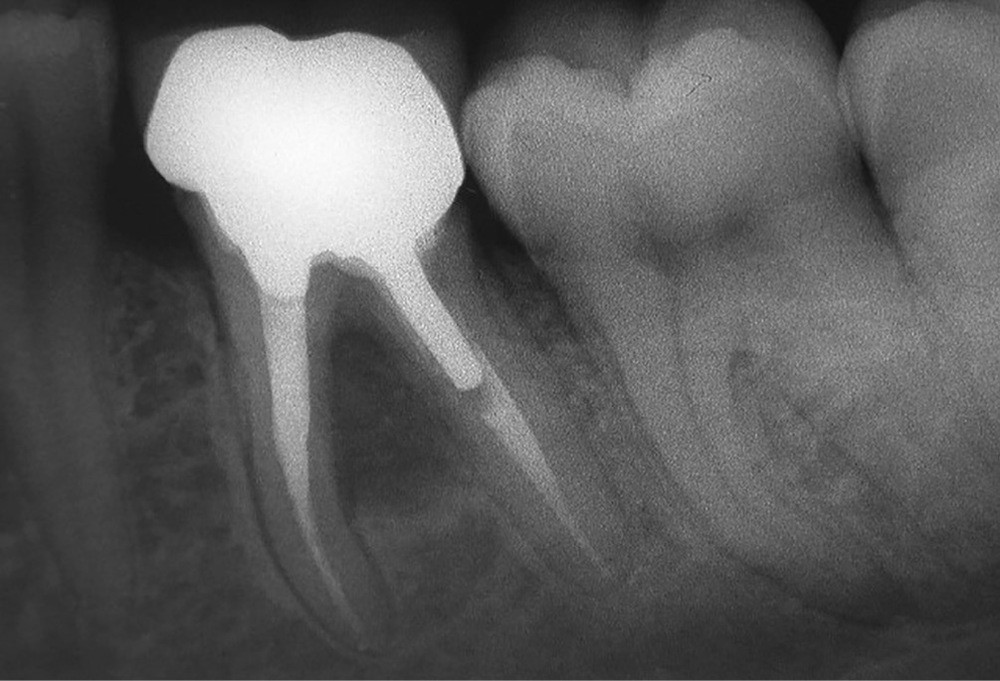

1. Radiographie préopératoire. Cas clinique présentant plusieurs difficultés : lésion de furcation volumineuse, perforation de la racine distale due à l’ancrage du tenon et stripping de la racine mésiale due à une mise en forme iatrogène.

Conserver ou extraire une dent est un dilemme quotidien du praticien qui doit pouvoir offrir une solution pérenne à son patient. Les critères essentiels à prendre en considération sont : l’intégrité de la structure dentaire (absence de fracture/fêlure), le plateau technique disponible (microscope opératoire, biomatériaux, ultrasons…) et les compétences du praticien. Si tous les critères mentionnés sont réunis, la solution conservatrice est une option thérapeutique fiable et qui montre des taux de succès équivalent à ceux des implants. Quel que soit le traitement réalisé conservation/extraction, le patient doit être partie prenante de la réflexion afin d’accepter la possible survenue de complication inhérente à l’exécution d’un acte médical.

Plus qu’une difficile question, le choix entre conserver et extraire est l’essence même d’une discipline conservatrice comme l’endodontie. Les moyens dont nous disposons pour faire notre choix sont : théorique, clinique, radiologique et technique (plateau et praticien).